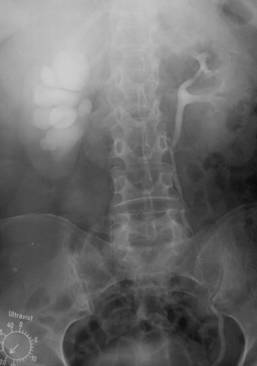

Fig. 60 – Rinichi in potcoava